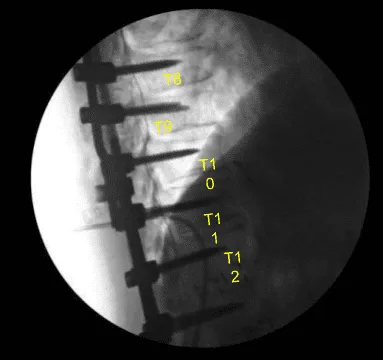

AP and lateral x-rays and final CT scan showed appropriate positioning of all the hardware. Morselized allograft with bone morphogenic protein was packed in lateral gutters on the left side for new fusion arthrodesis. Vancomycin powder was applied. Hemostasis was confirmed. A medium size Hemovac drain was tunneled in a subfascial manner and secured to the skin with a nylon suture.

Axial view Thoracic spine postoperative X-ray